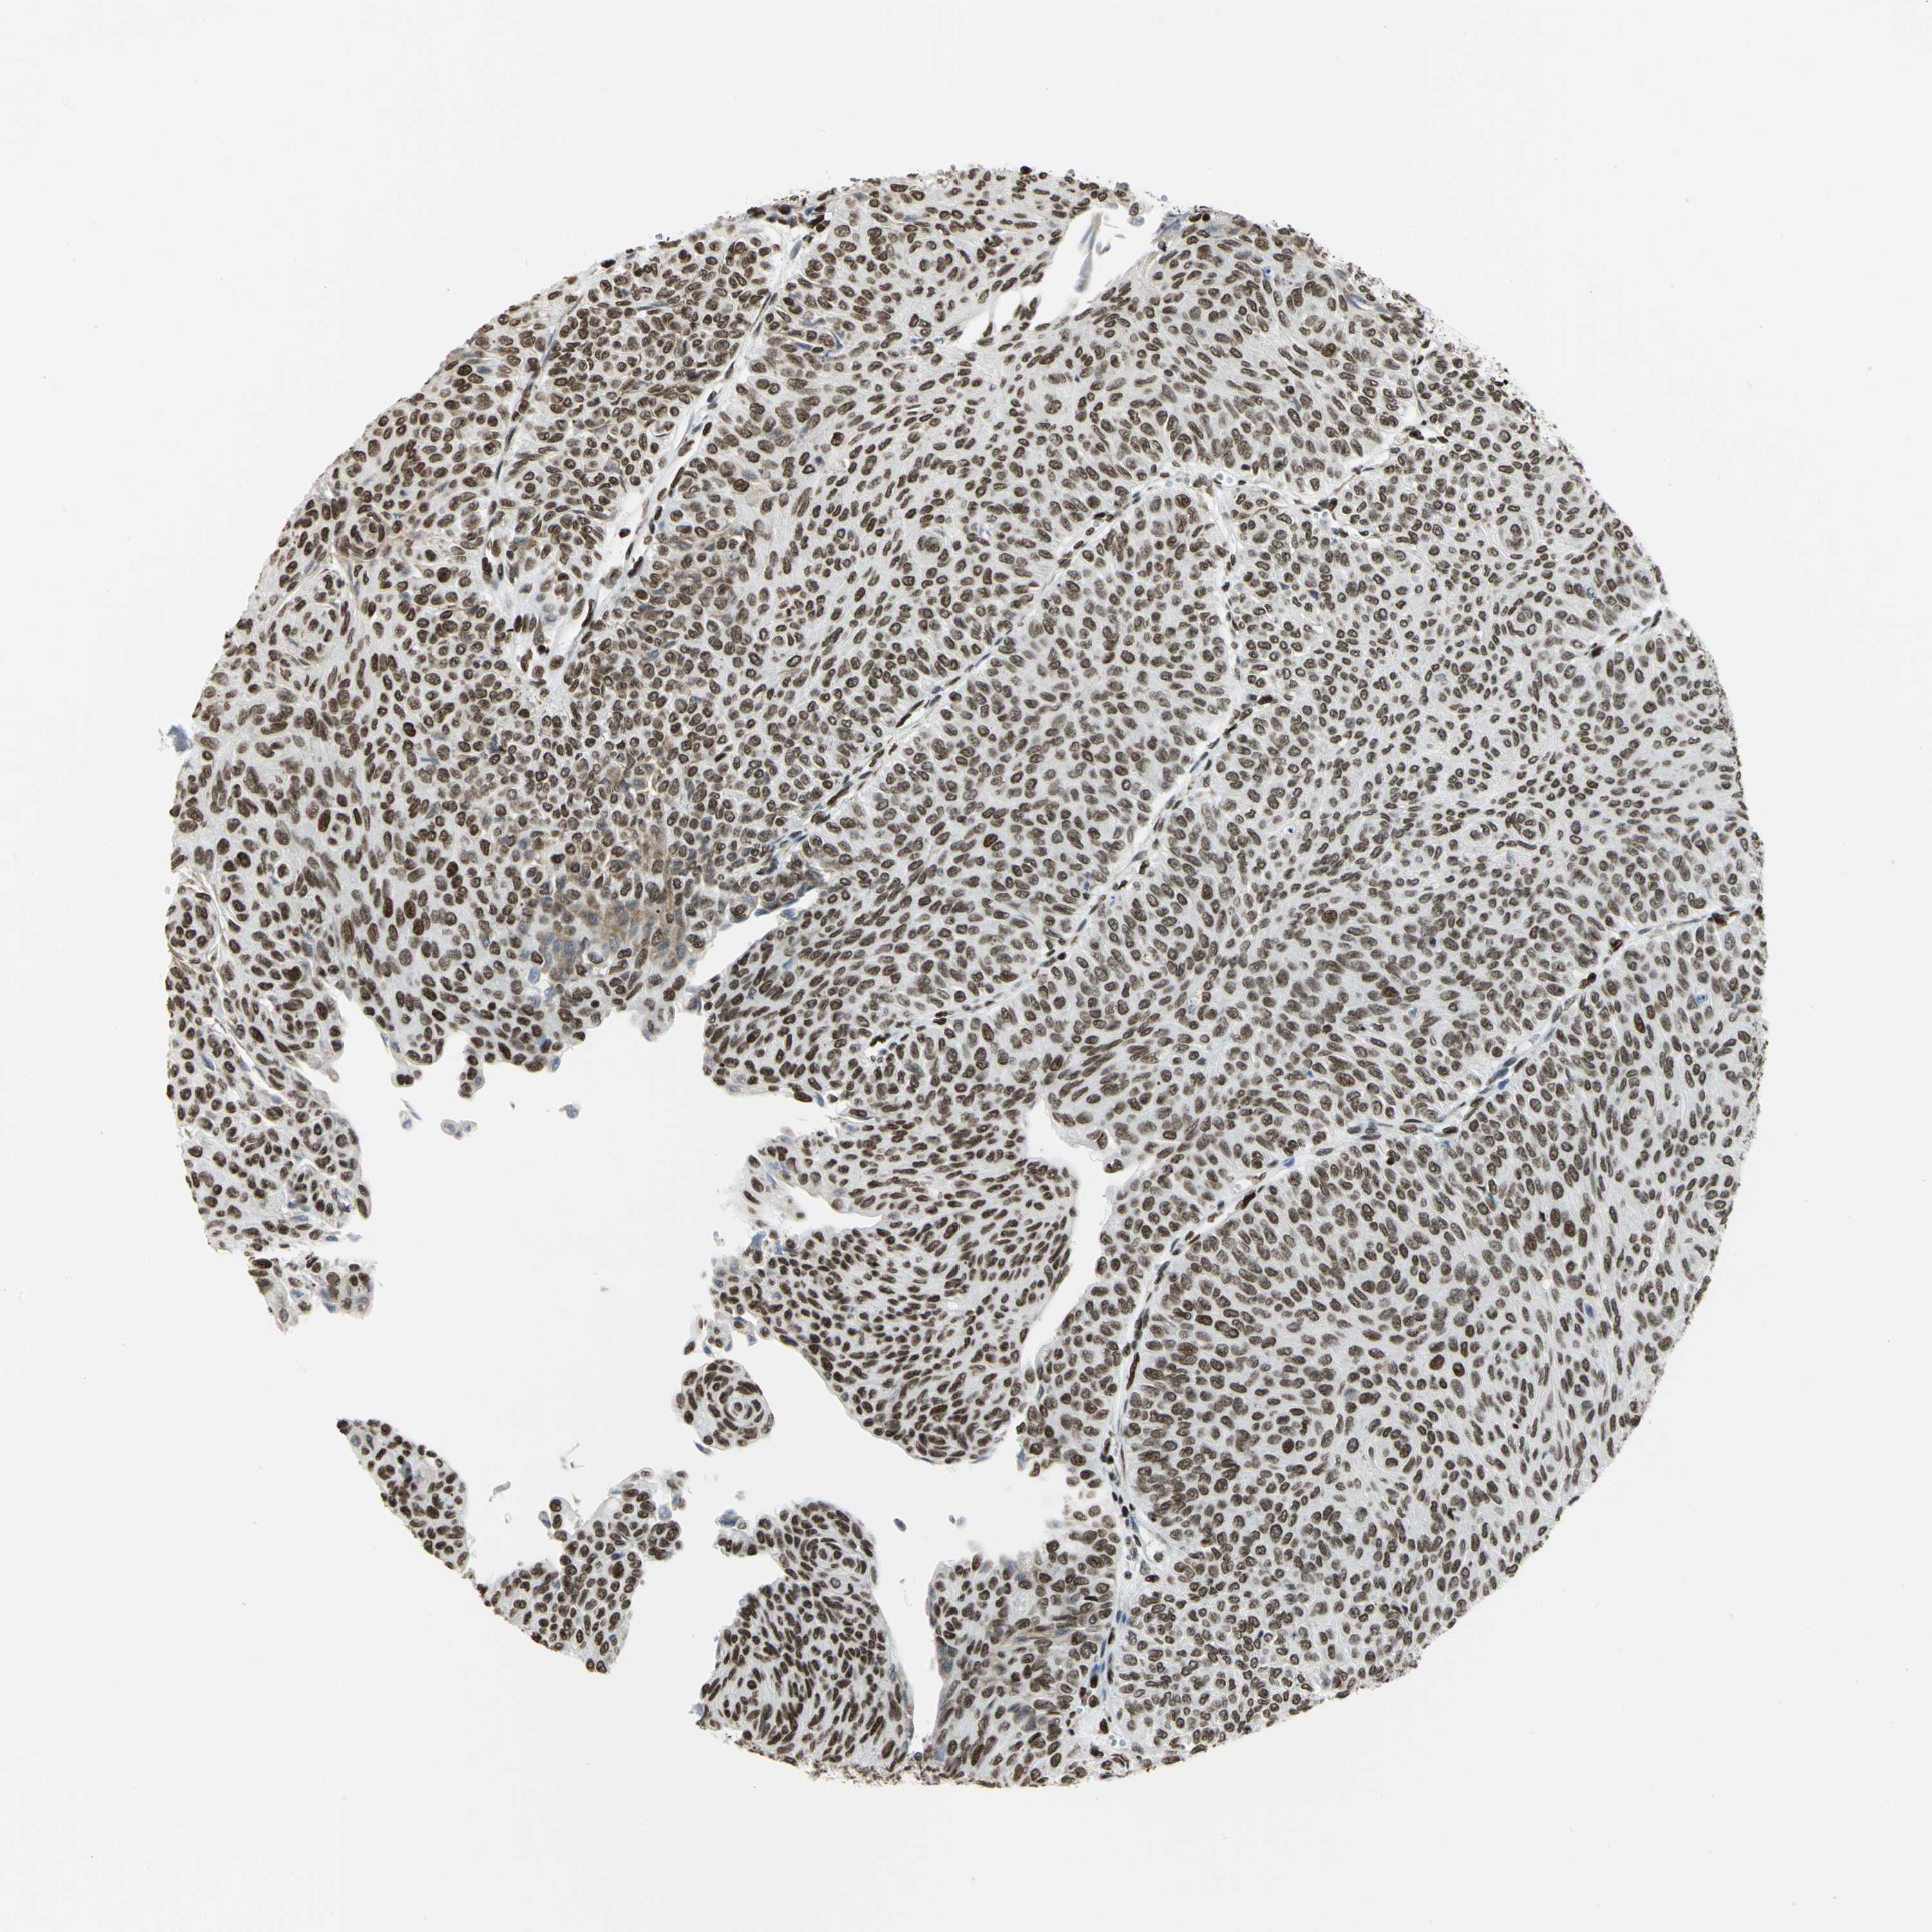

UROTHELIAL CANCER - Protein expressioni

A mouse-over function shows sample information and annotation data. Click on an image to view it in a full screen mode. Samples can be filtered based on level of antibody staining by selecting one or several of the following categories: high, medium, low and not detected. The assay and annotation is described here.

Note that samples used for immunohistochemistry by the Human Protein Atlas do not correspond to samples in the TCGA dataset.

Antibody stainingi

Antibody staining in the annotated cell types in the current human tissue is reported as not detected, low, medium, or high, based on conventional immunohistochemistry profiling in selected tissues. This score is based on the combination of the staining intensity and fraction of stained cells.

Each image is clickable and will lead to virtual microscopy that enables deeper exploration of all samples and also displays staining intensity scores, fraction scores and subcellular localization as well as patient and tissue information for each sample.

Antibody HPA003506

Antibody CAB005873

Urothelial carcinoma, High grade

Urothelial carcinoma, Low grade